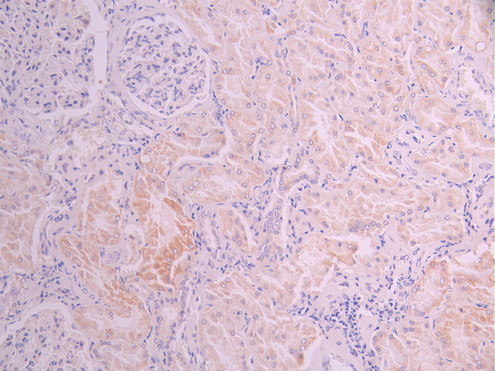

IHC image of CSB-RA597662A0HU diluted at 1:100 and staining in paraffin-embedded human liver cancer performed on a Leica BondTM system. After dewaxing and hydration, antigen retrieval was mediated by high pressure in a citrate buffer (pH 6.0). Section was blocked with 10% normal goat serum 30min at RT. Then primary antibody (1% BSA) was incubated at 4°C overnight. The primary is detected by a Goat anti-rabbit polymer IgG labeled by HRP and visualized using 0.05% DAB.